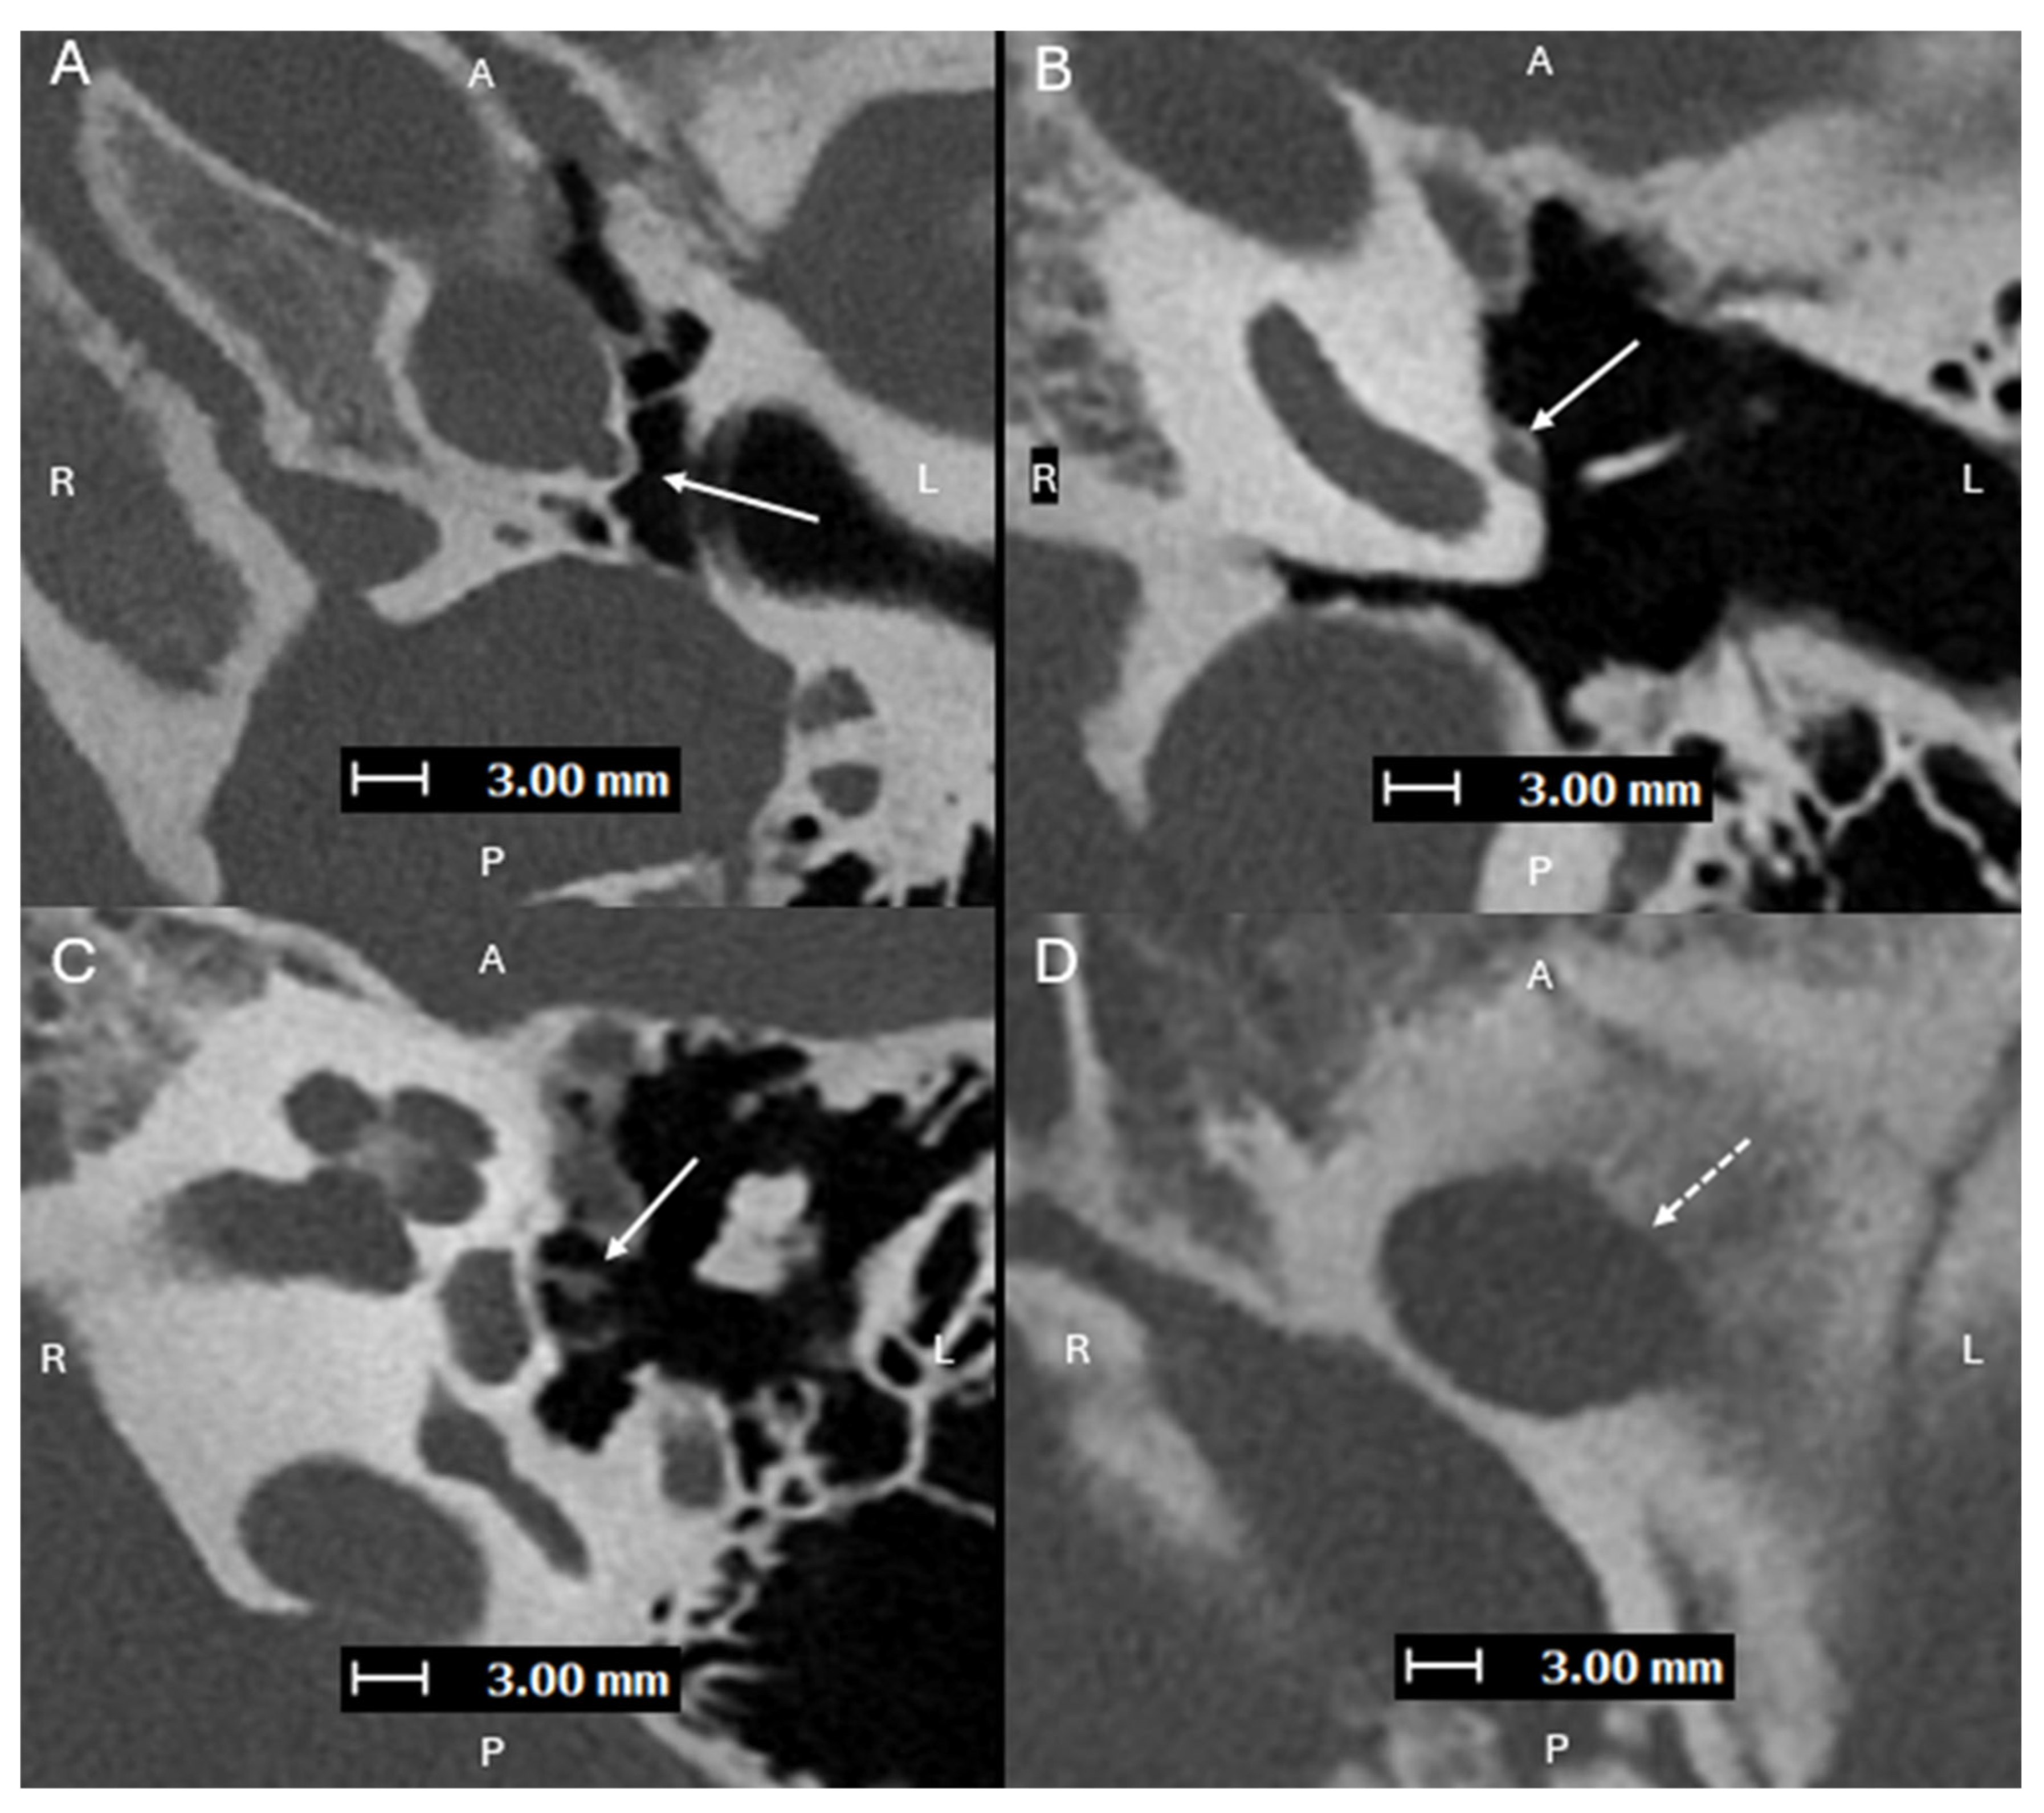

Figure 1. Axial images (superior to inferior (A,B), with A, P, L, R for orientation donating anterior, posterior, left, and right respectively) from a PCD-CT (Naeotom Alpha; Siemens Healthineers, Forchheim, Germany) temporal bone study—with UHR mode (Collimation 120 × 0.2 mm), Tube voltage (120 kVp), slice thickness/increment (0.2/0.1 mm), and sharp Kernel (Hr84) with Quantum Iterative Reconstruction (3)—demonstrating a normal left inferior tympanic canaliculus ITC (solid arrows) passing between the carotid canal and jugular foramen, traveling along the cochlear promontory. The normally small inferior tympanic artery extends through the ITC and is a branch of the external carotid artery, usually the ascending pharyngeal artery. Normally, the ITC, as in this case, is a thin corticated channel that transmits the tympanic branch of the glossopharyngeal nerve (Jacobson’s nerve) and the inferior tympanic artery. The latter is hard to visualize on EID-CT due to its small size. It can enlarge in case of congenital involution of the cervical portion of the internal carotid artery (ICA), forming the aberrant ICA [1,2].